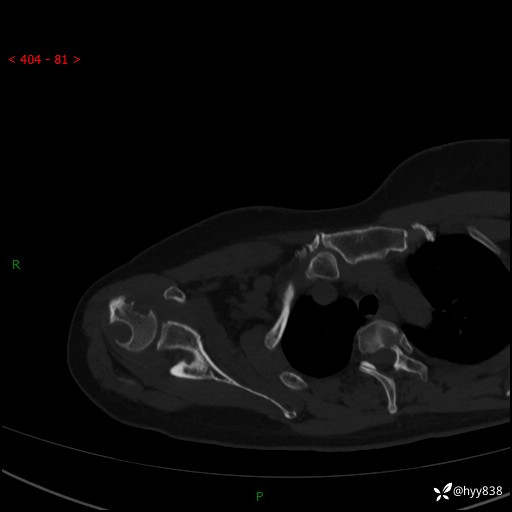

中年女性,发现右肩关节占位2天。有特征、有细节---结果公布~

年龄:47岁

主诉:发现右肩关节占位2天

现病史:患者3年前摔伤致右肩部疼痛,未行特殊处理,后右肩活动时轻度疼痛,患者未引起重视。1月前上述症状加重,于当地县人民医院就诊,2023-07-10右肩关节MR:右肱骨头、肩胛骨及周围软组织异常信号。现患者右肩可触及质硬包块,活动时疼痛,无头晕头痛、恶心呕吐、腹痛腹胀等,为求进一步治疗,来我科就诊,门诊以“右股骨占位性病变”收入我科。 起病以来,患者精神、饮食、睡眠可,大小便正常,体力、体重未见明显变化。

右肩关节CT平扫